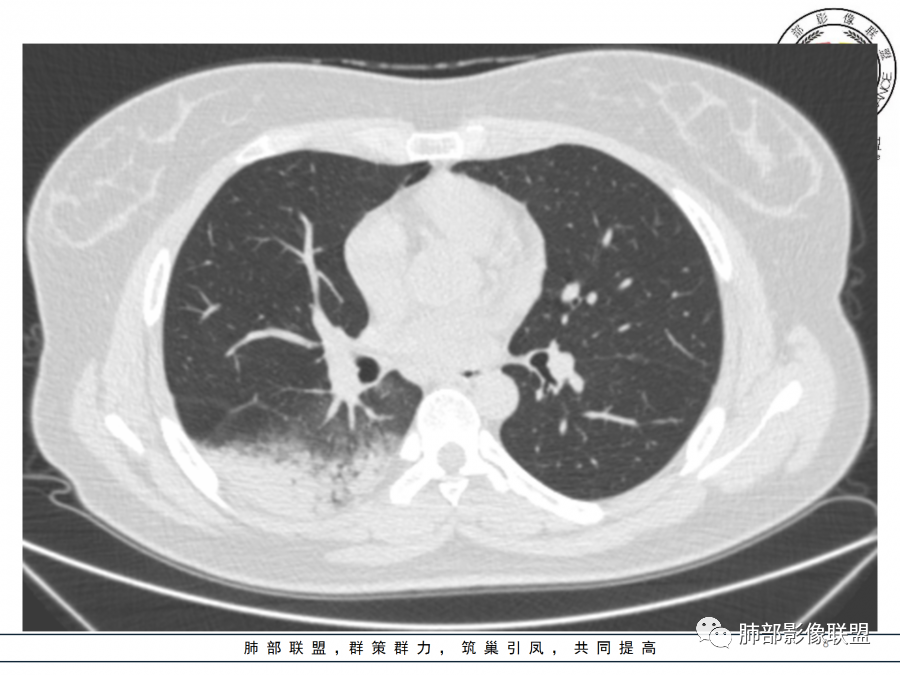

右肺胸膜下实变,病变跨多个叶生长,宽基底与胸膜相连,近端支气管穿行病灶内,并可见片状磨玻璃影,边界清,部分远端小支气管堵塞,支气管略有扩张,周围散发小结节,临床年轻女性,炎性指标高,发热六日,首先考虑感染性病变(肺链,奴卡,隐球,OP)鉴别淋巴瘤。

年轻女性,无明显诱因发热,体温略高,起病较急,有畏寒,右下肺紧贴胸膜下片状实变影,部分融合,外围有结节影,性质比较单一,类似于蘑菇兄弟,病灶周围伴有晕,支气管进入近端扩张远端堵塞,常规考虑感染,肺炎链球菌、隐球菌。

青年女性,发热咳嗽5天,炎症标志物升高。右肺下叶大片实变伴周围GGO,GGO内未见细网格,主体与胸膜平行,似多个病灶融合,实变区内见支气管部分进入,部分支气管受压狭窄,周围可见多发卫星病灶。支持炎性,考虑隐球感染,鉴别op。

年轻女性,急性起病,咳嗽,发热,黄痰,白细胞高,CRP基本正常,基础体健。CT提示右肺下叶实变,宽基底与胸膜相连,长轴平行于胸膜,可见支气管充气征,于病变中央截断,走形自然,胸膜下脂肪间隙可见,倾向于隐球菌,鉴别肺链,军团菌等。

年轻患者,右肺下叶大片状实变影,长轴与胸膜平行,内见含气支气管征,周围磨玻璃晕影。考虑感染性病变,隐球?

病灶长轴与胸膜平行,边缘有晕,病灶融合趋势,支气管进入,走行自如,考虑隐球菌肺炎。

年轻女性,急性发病,咳嗽咳痰五天,炎性指标升高,右肺下叶胸膜下大片实变影,周围见磨玻璃影,边界清晰,长轴与胸膜平行,呈融合趋势,支气管进入走行自然,远端截断,考虑炎性,隐球菌可能。

年轻女性,发热,急性发病,白细胞高,右肺下叶大片实变,长轴与胸膜平行,内见支气管走行,远端截断,周围有晕,晕边界清,考虑感染,隐球可能,鉴别淋巴瘤。

年轻女性,右肺下叶胸膜下多发实变、结节影,宽基底与胸膜相连,边缘模糊不清,实变内见支气管穿行,血象高,考虑感染性病变,大叶性肺炎?隐球?

青年女性,发热咳嗽急性起病,右肺下叶大片状实变密度影,长轴平行于胸膜,边缘模糊可见磨玻璃影及高密度结节影,实变内可见支气管穿行,直达病灶远端,考虑感染性病变,隐球菌可能大。

右肺胸膜下实变,病变跨多个叶生长,相互融合,宽基底与胸膜相连,支气管气象,并可见片状磨玻璃影,边界清,炎性指标高,发热六日,考虑感染病变,链球菌?腺病毒待排。

右肺下叶大片状实变影,长轴平行于胸膜,边缘模糊可见磨玻璃影,支气管进入,部分近端阻塞,考虑感染性病变,隐球菌,鉴别大叶性肺炎。

年轻女性,起病急,白细胞,C反高,存在感染。右下肺大片实变影,支气管充气征,长轴平行胸膜,似多个病灶融合,周围GGO,部分清,部分不清。考虑感染,隐球可能。

青年人,右肺多发团片状阴影,边缘模糊,周围可见磨玻璃影,内部有支气管空气征,考虑感染性病变,隐球菌感染可能。

右肺下叶大片状实变影,从外向内,长轴平行于胸膜,边缘模糊,可见磨玻璃影,支气管进入,远端部分阻塞,考虑感染性病变,隐球菌,鉴别淋巴瘤。

26岁,女性,发热、咳嗽5天。咳少量黄痰,起病急,病程短,白细胞及中性高,血沉及D-二聚体增高。胸部CT:右肺下叶大片实变,长轴沿胸膜分布,宽基底与胸膜接触,边界不清,周围GGO,部分团片影融合,病灶内可见支气管充气征,部分支气管进入病灶后阻塞。考虑:感染性病变,隐球菌?脓毒肺栓塞?鉴别:肺炎型肺Ca。

年轻女性,右肺下叶一大片实变影,似有多个结节影融合,周围有晕,内见支气管充气征,部分支气管进入后截断,病变近胸膜,长轴胸膜平行,考虑炎性,隐球菌首先考虑。

青年女性,影像表现右肺下叶胸膜下大片状实变影,近端见充气支气管征,边缘见片状磨玻璃影,下叶背段尚可见一结节。考虑感染性病变,隐球菌感染可能。

右下肺大片实变影,空气支气管征,边缘GGO,小叶间隔增厚,周围有蘑菇兄弟,基底宽,与胸膜平行,考虑隐球菌感染,鉴别肺炎型肺癌。

晨读:年轻女性,右肺胸膜下实变影,平行于胸膜,边缘磨玻璃影,内见支气管充气征,走形自然,略扩张。考虑感染性改变,隐球,肺链。2月发病,病毒性肺炎要考虑。鉴别淋巴瘤。

晨读:年轻女性,发热咳嗽5天。白细胞计数升高。右肺下叶大片状高密度影,边缘模糊,有实变 GGO,其内见支气管气相、无受压变细,无枯枝表现,其近端支气管无异常,右肺下叶背段见结节状影,定性考虑:炎症,隐球菌感染可能,炎症型肺癌不支持。

右下肺胸膜下大片状高密度影,其长轴与胸膜平行,病灶近端GGO模糊,部分支气管进入后阻断,支持感染性病变,考虑隐球菌